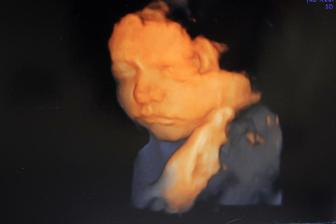

12.02.2011 dnes bol super deň, po dlhej dobe sme videli malého,mala som masáž bruška :D nožičky mal až pri hlavičke čo vystrájal netuším, aj sa mu štikútalo,len ja som nič necítila :°( ale super správička drobček je otočený hlavičkou dole,28+6tt máme 1197g a všetko vyzerá v poriadku :°) aj fotos nám pán dr. dal :°)